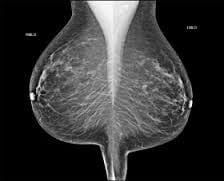

La

Mammografia Digitale rappresenta oggi lo standard più avanzato nella diagnostica senologica, avendo quasi completamente sostituito la vecchia mammografia analogica. L'evoluzione più significativa è rappresentata dalla

Mammografia con Tomosintesi non solo aumenta la precisione diagnostica, ma consente anche una compressione della mammella più confortevole e un dosaggio di radiazioni mantenuto al minimo indispensabile, secondo i protocolli di sicurezza di

Servizi Diagnostici Integrati.